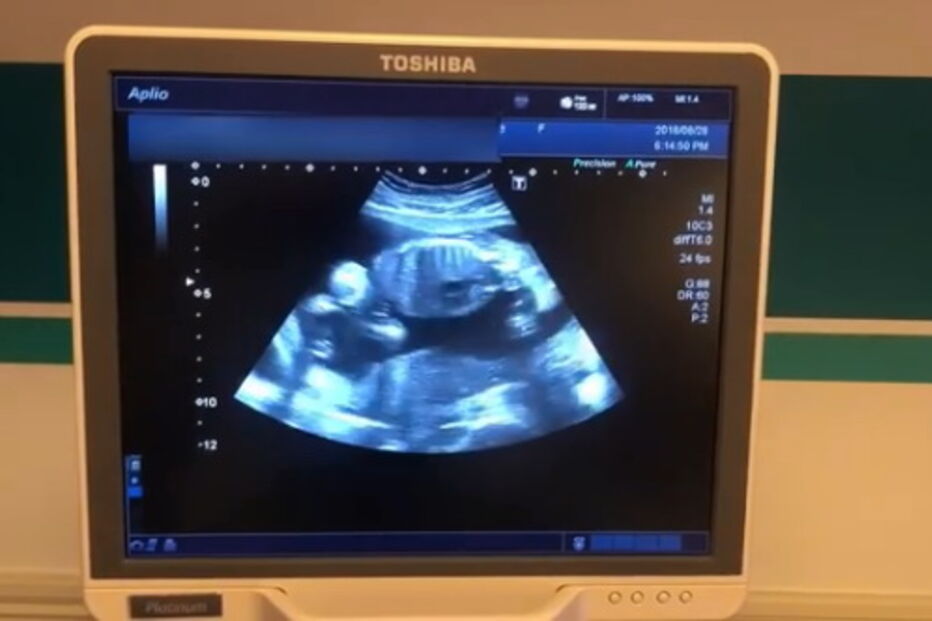

Atriz de 36 anos está grávida do primeiro filho.